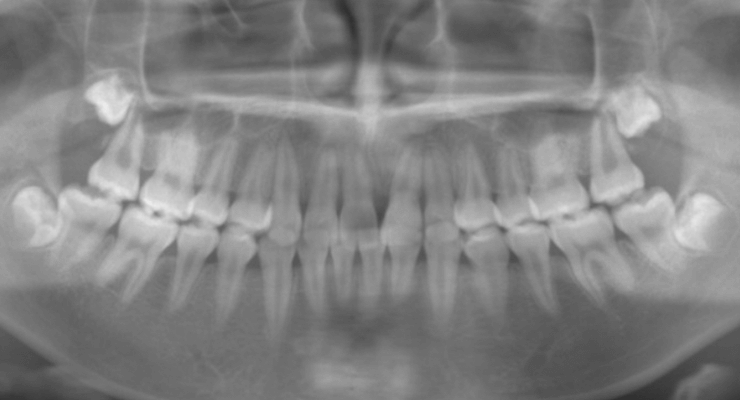

5埋伏歯

主訴:永久歯が出てこない(患者年齢11歳3か月)

診断名:左側上顎埋伏犬歯、左側上顎中切歯歯根吸収

治療に用いた主な装置:リンガルアーチ、マルチブラケット装置

抜歯部位:左側上顎中切歯、左側上顎乳犬歯

治療期間:2年9か月

初診時

パノラマX線写真